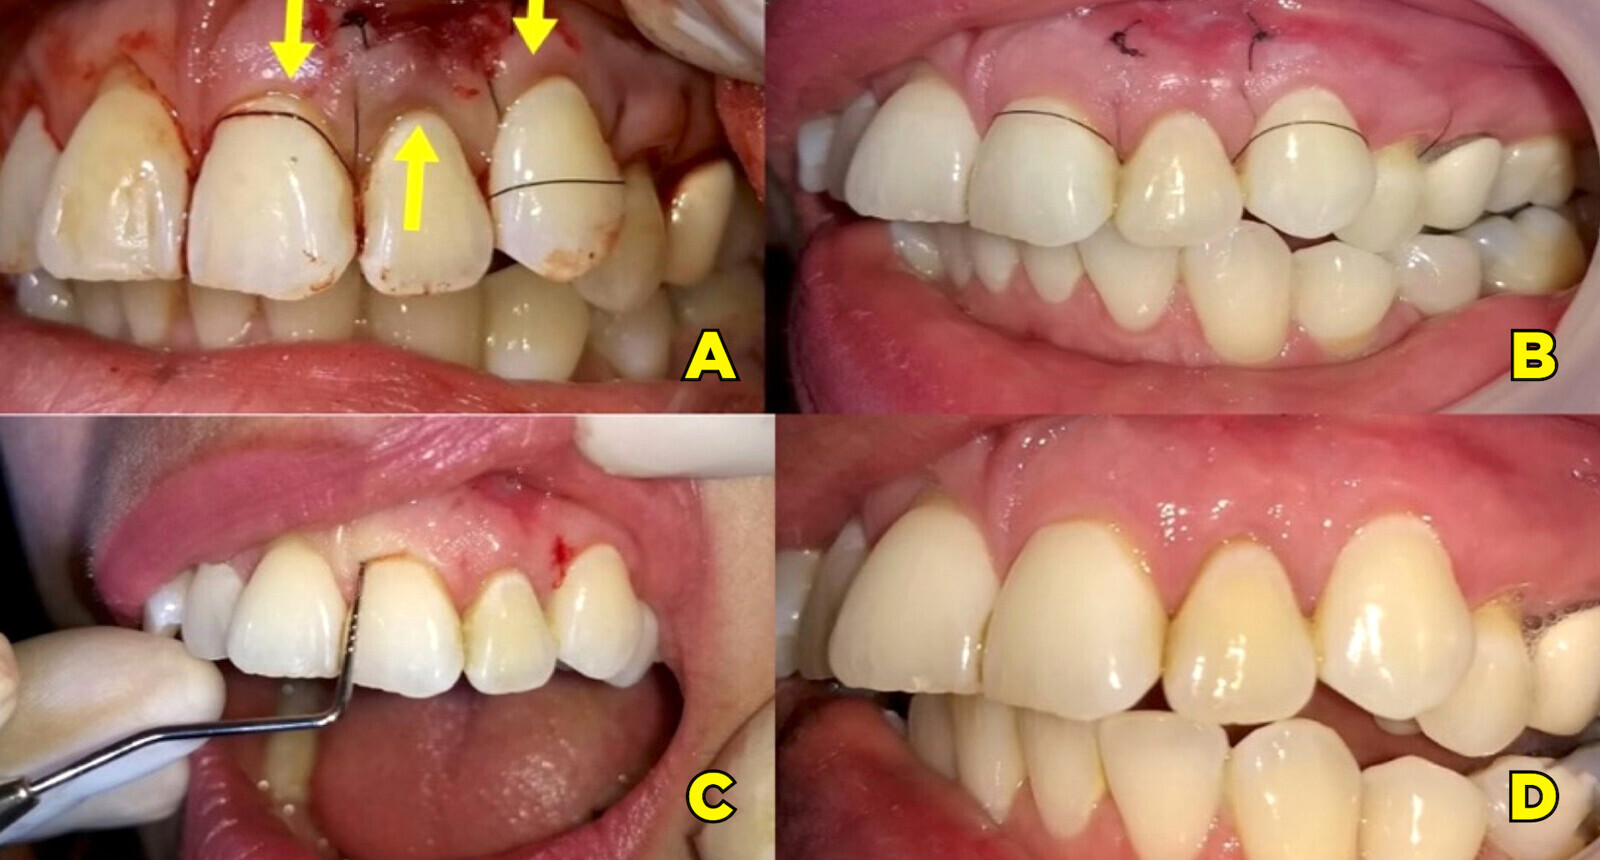

Figura 2. Tras la desobturación previa en el diente 22 en la Sesión 1, en la Sesión 2 (A), se procedió a anestesiar con lidocaína y epinefrina al 2%. Abordaje quirúrgico con la técnica de Parchs (B).

Figura 3. Osteotomía (A). Extirpación del material sobreobturado y remanente del periápice y posterior limpieza del lecho con legrado noble (B).